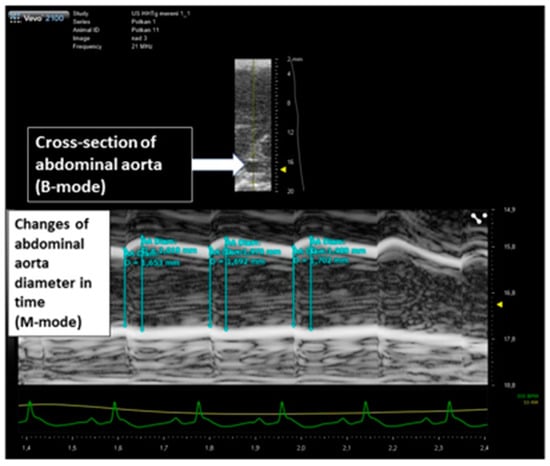

2.1. Changes of Cardiovascular Parameters after Ovariectomy and Estradiol Substitution

4.2. Ultrasound Studies

- Knipp, B.S.; Ailawadi, G.; Sullivan, V.V.; Roelofs, K.J.; Henke, P.K.; Stanley, J.C.; Upchurch, G.R., Jr. Ultrasound meas-urement of aortic diameters in rodent models of aneurysm disease. J. Surg. Res. 2003, 112, 97–101. [Google Scholar] [CrossRef]